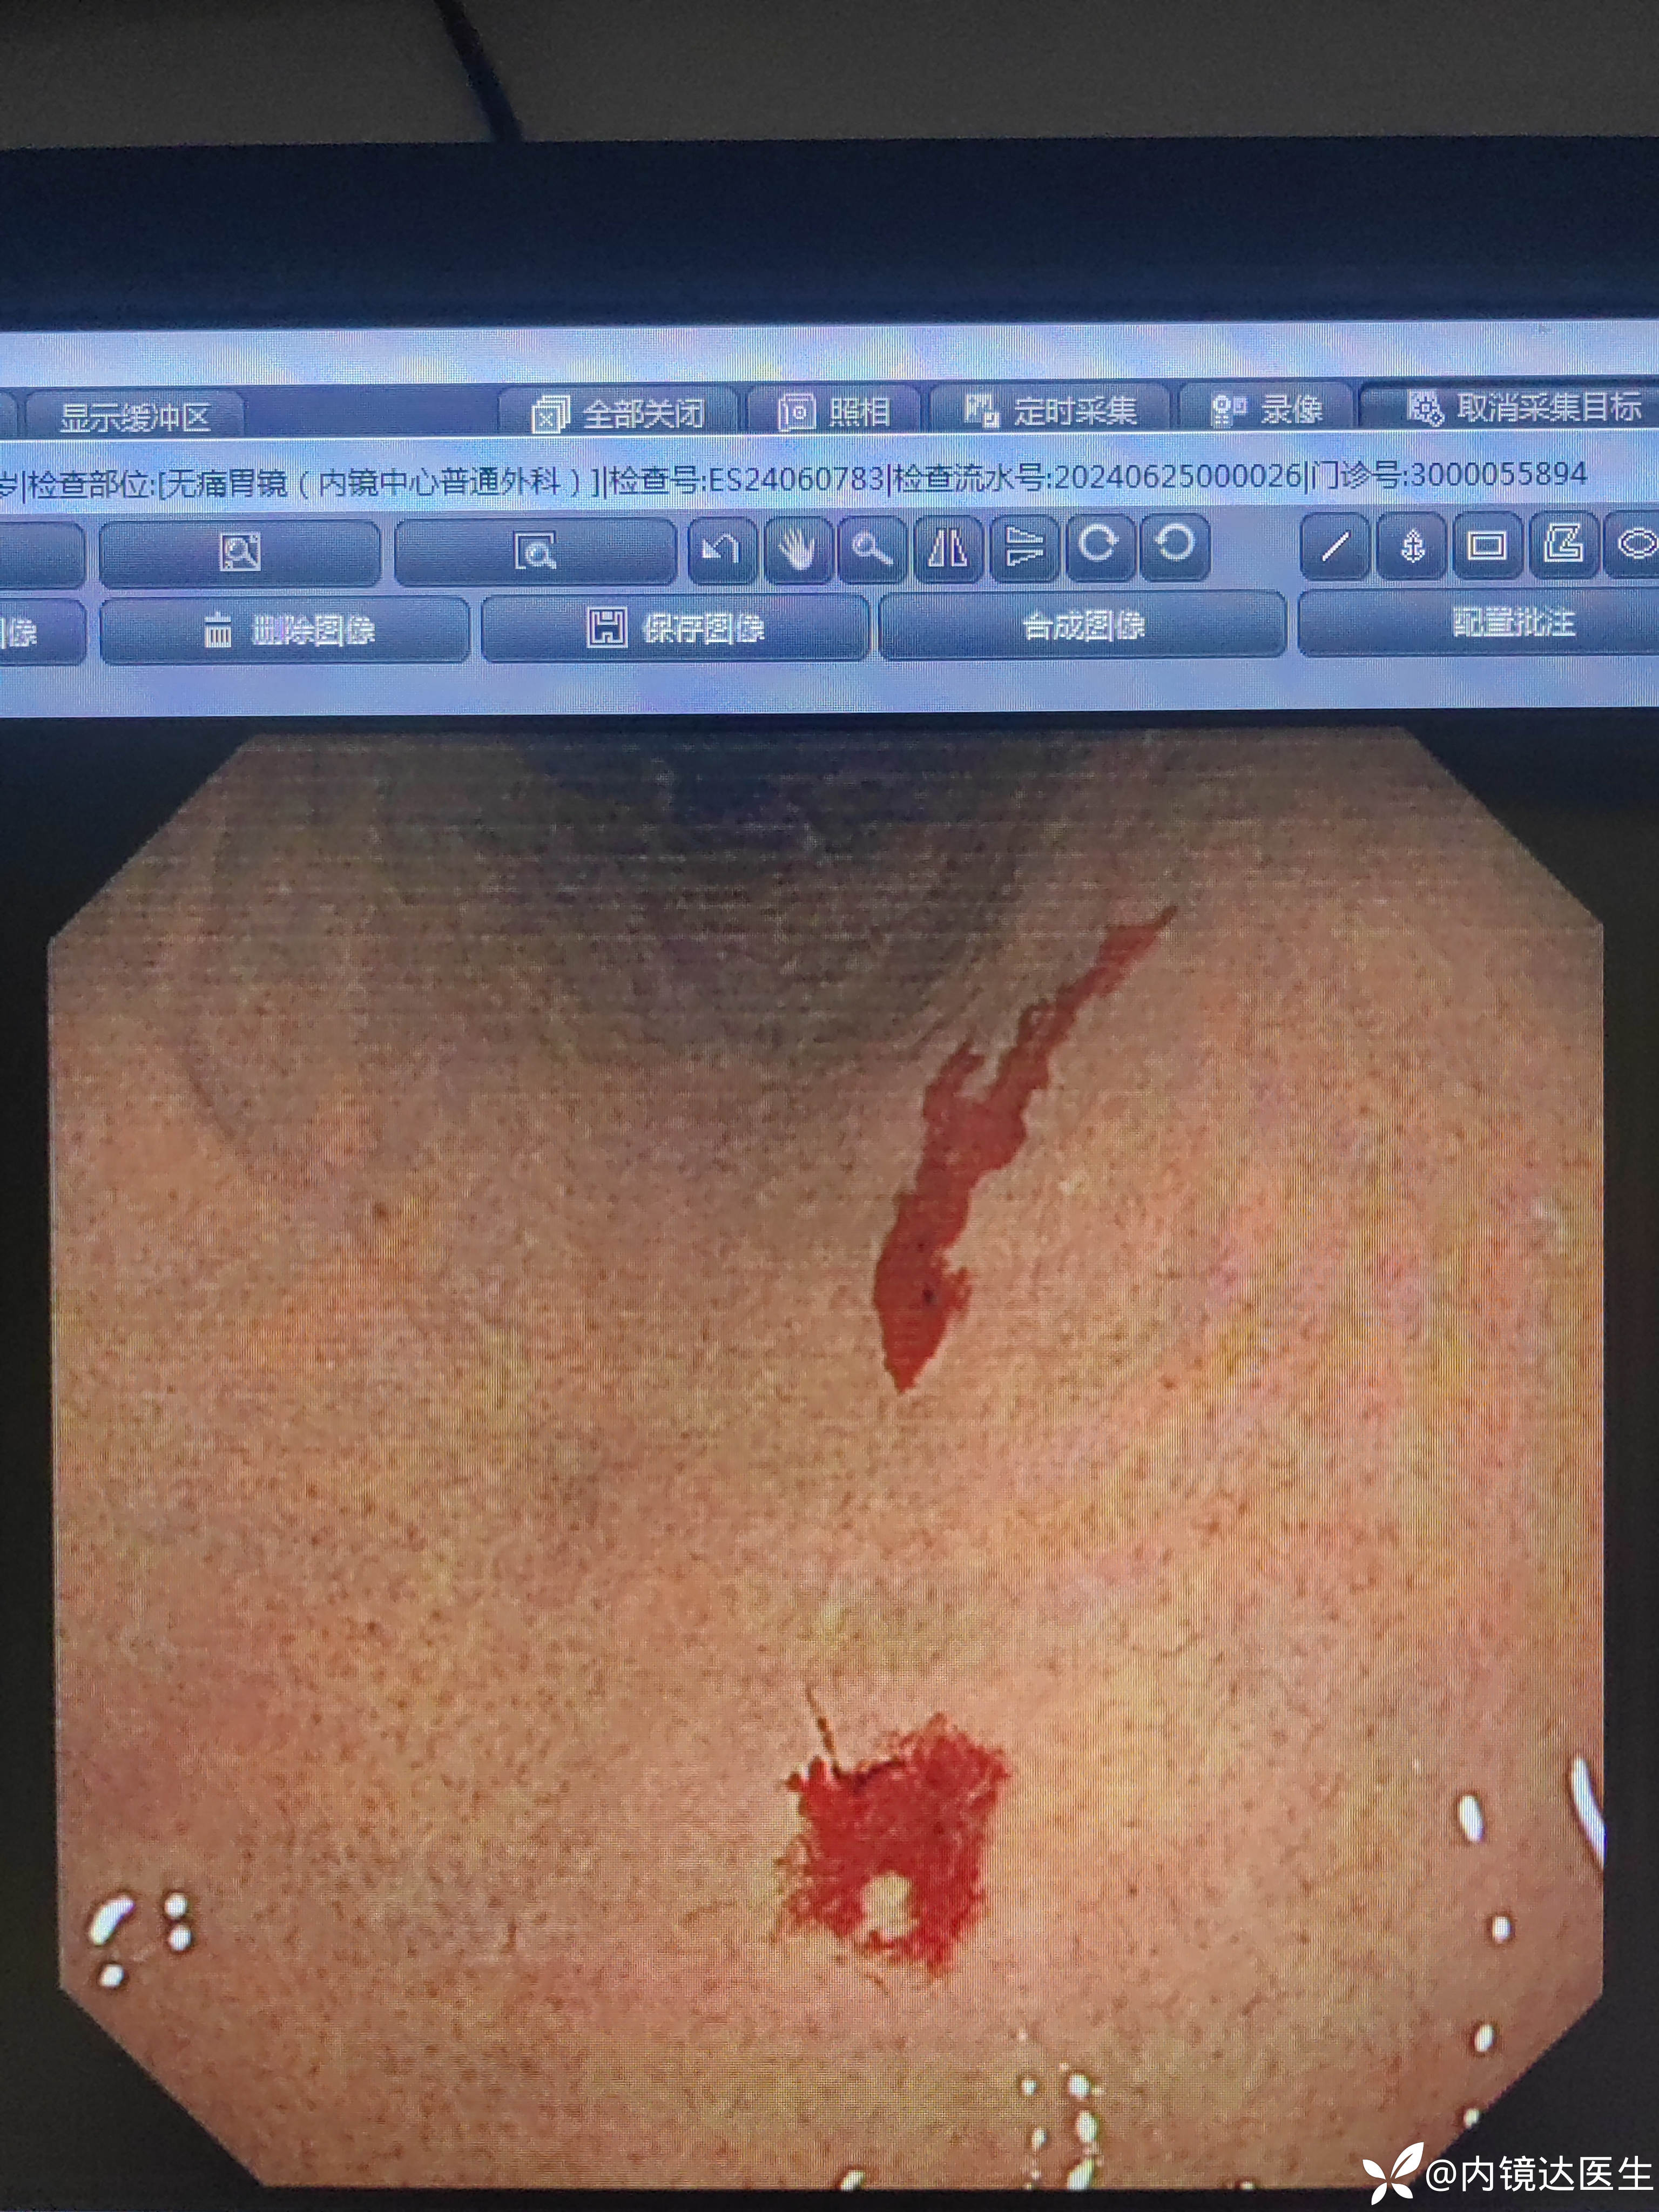

胃镜检查示声带见少量新鲜渗血,体小多发毛细血管扩张,中等量充气后发现毛细血管扩张处见活动性渗血,可自行停止

血常规提示缺铁贫,所以贫血应该是因为慢性失血导致的,胃毛细血管扩张处自发性出血可能是贫血原因,评论中建议可用APC治疗。

遗传性出血性毛细血管扩张症,为常染色体显性遗传,以局部毛细血管扩张和扭曲为特征。主要临表为皮肤、粘膜等部位毛细血管扩张,局部反复出血及贫血等,还可伴随动静脉畸形(这段引自消化道常见病内镜诊断图谱第二版 p009 一听大师主编)。